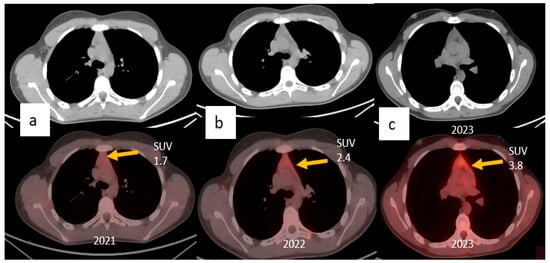

2. Case Presentations

3.2. Thymic Hyperplasia in COVID-19 Infection and Vaccination and the Role of Multimodality Imaging